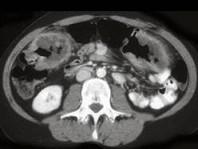

男,55岁,腹部胀痛不适一月余,CT检查如图,最可能的诊断是 ( )A.结肠结核B.结肠淋巴瘤C.结肠转移瘤D.假膜性结肠炎E.横结肠癌

问题 男,55岁,腹部胀痛不适一月余,CT检查如图,最可能的诊断是 ( )

选项 A.结肠结核 B.结肠淋巴瘤 C.结肠转移瘤 D.假膜性结肠炎 E.横结肠癌

答案 E